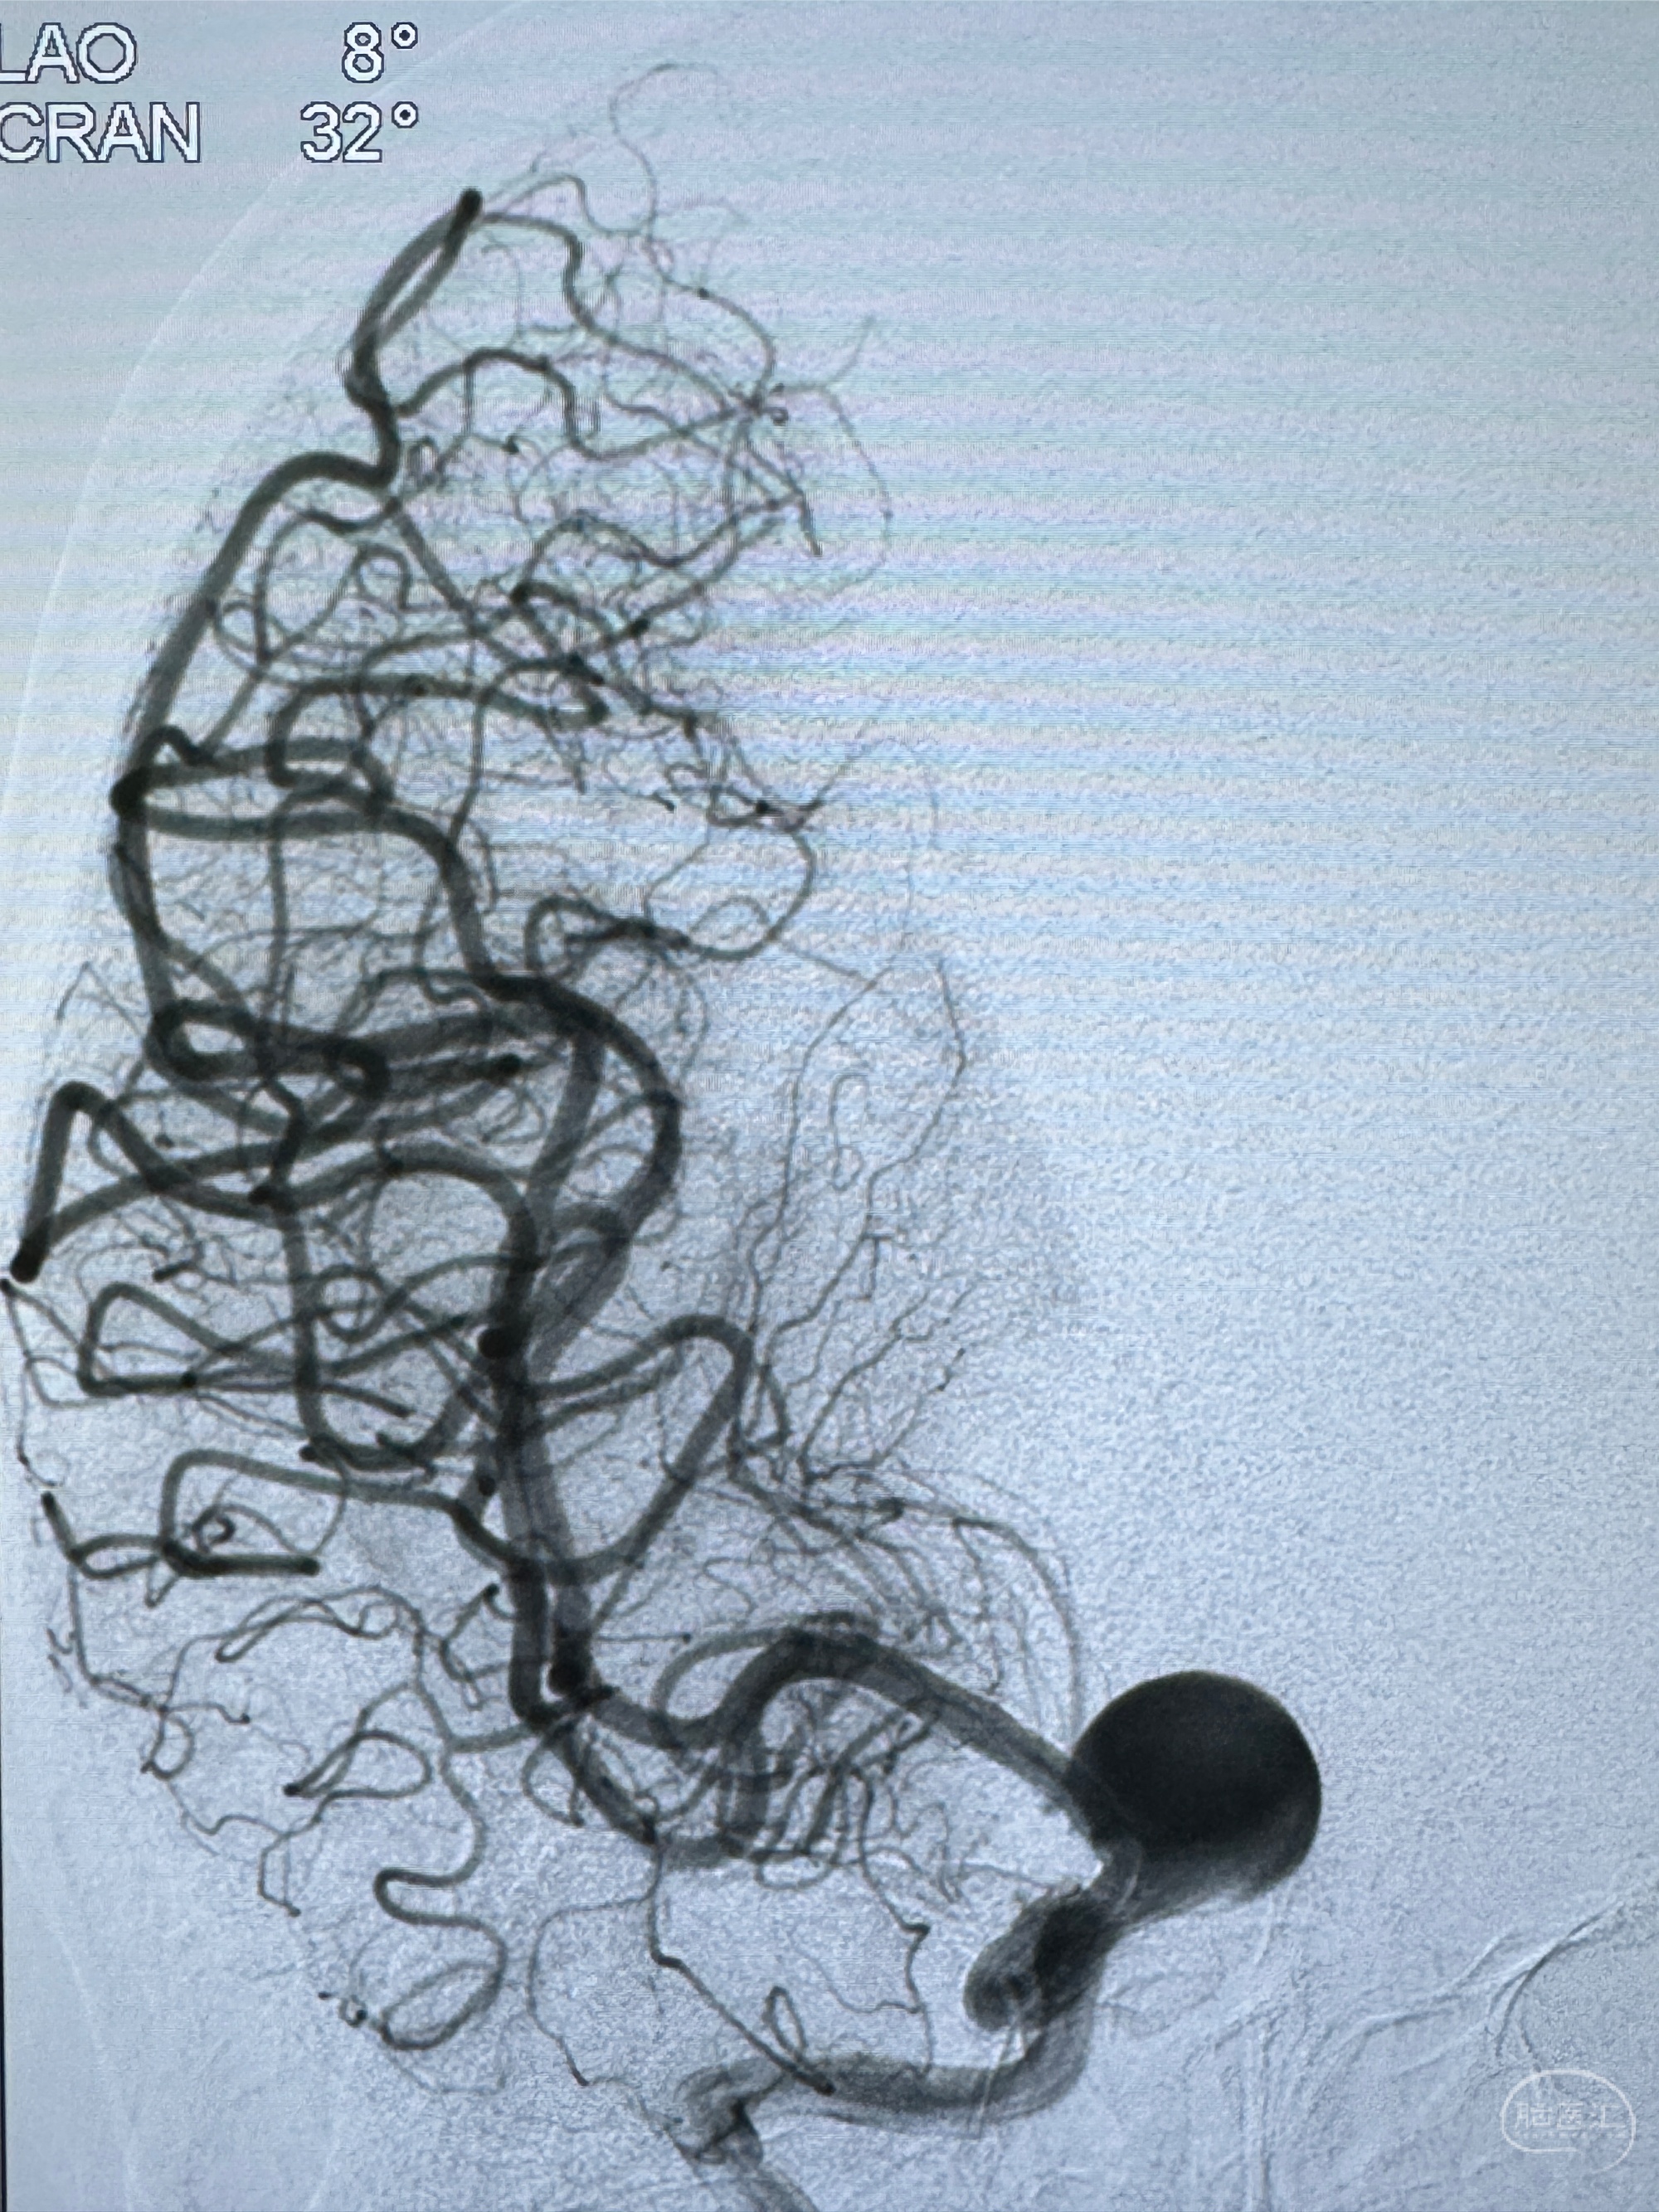

2023-12-27术后第十天复查DSA

支架贴壁佳,但可见射流,咋办?

2024-01-08全麻下再行植入密网支架一枚

Tubridge 4.5-35mm

支架植入顺利,贴壁佳,支架内血流通畅,动脉瘤内血液滞留明显